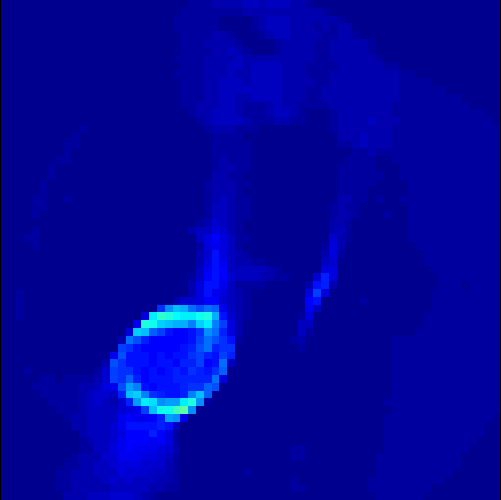

5.2 Monte Carlo Simulation

In order to test the behaviour of the proposed method in a more realistic, random-based test case, we performed a Monte Carlo simulation for dynamic SPECT imaging. First, we created a simple image phantom consisting of an outer and two inner circles which represents the structure of the region of interest (see figure 8(a)). Within those regions we assumed concentration curves over a time period of 90 time steps as displayed in figure 8(b). Based on the tracer intensity in an image frame at each time step, we created a variable number of random decay events (where the number is proportional to the average concentration in one pixel in the whole image frame per time step) with a probability proportional to the concentration in every subregion. They are detected by a virtual double head gamma camera rotating around the patient by 46 degrees per time step, which consists of 374 detector bins. Every simulated decay event is projected onto the scanner and counted by the corresponding detector bin.

In two different tests we fixed the number of events counted by the detector equal to (resp. ) times the average concentration in one pixel. The resulting sinogram images of the accumulated counts in each bin are shown in figure 9.

Based on the sinogram data we applied the proposed algorithm in order to reconstruct the original image sequence. The results for both test cases are shown in figure 10.

As one can see, the method is able to reconstruct the regions properly, even in case of a low count number. Within a number of iterations (average of 100 outer and 10000 inner iterations), the algorithm presents a reasonable reconstruction of the region of interest and the corresponding regional tracer concentration curves. Here, the parameters were not optimized as in the case of the synthesized data sets in the previous section, but kept fixed as , and . With futher optimized parameter values one could possibly provide even better results.